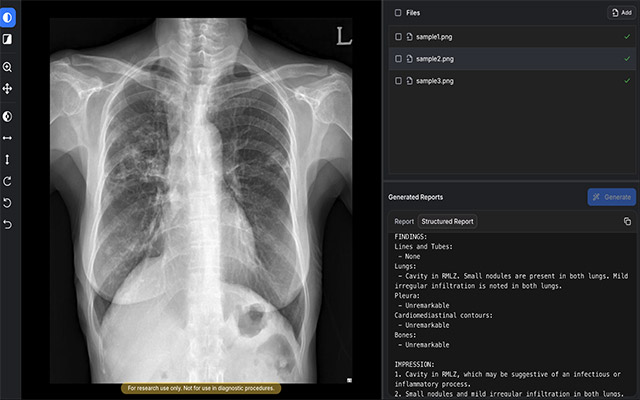

• AIRead-CXR이 흉부X선 영상을 분석해 예비소견서를 생성한 화면 예시 /이미지=숨빗AI

▲ AIRead-CXR이 흉부X선 영상을 분석해 예비소견서를 생성한 화면 예시 /이미지=숨빗AI

AIRead-CXR은 흉부X선 영상을 분석해 영상 소견을 문장 형태의 예비소견서로 생성하는 소프트웨어 의료기기(SaMD)다. 기존 의료영상 AI가 병변 검출이나 이상 여부 판단에 집중해 온 것과 달리, 판독 결과를 보고서 형태의 초안으로 작성하는 기능을 갖춘 것이 특징이다.